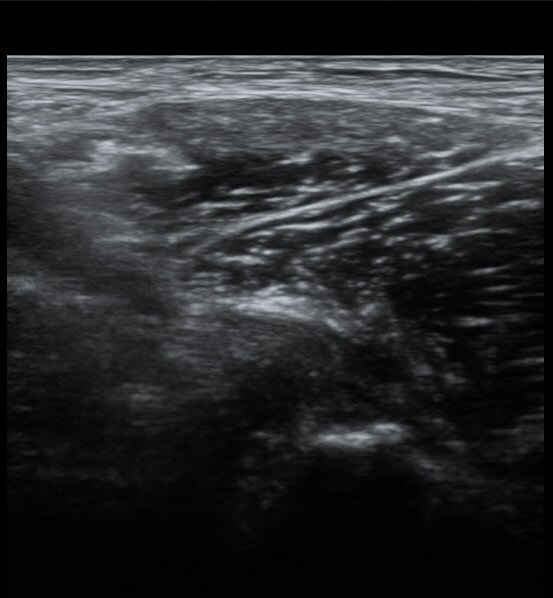

Àü»óÀå°ñ±Ø(ASIS) ¿¡¼­ 2~3cm ¾Æ·¡, 1~2cm ³»Ãø  ÀüÇÏÀå°ñ±Ø(AIIS) Á¾´Ü¸é°Ë»ç¿¡¼­

´ëÅðÁ÷±Ù ÈûÁÙÀÌ °í¿¡ÄÚ·Î Á¤»óÀûÀ¸·Î °üÂûµÇ³ª »À ºÎÂøºÎ¿¡ Àú¿¡ÄÚ º¯È­¸¦ º¸ÀδÙ(»çÁø 1).

ŽÃËÀÚ¸¦ Á¶±Ý ³»ÃøÀ¸·Î À̵¿ÇÏ´Ï ÈûÁÙÀÇ °í¿¡ÄÚ°¡ ¼Ò½ÇµÇ¾î º¸ÀδÙ(»çÁø 2, 3)

ÀÌ º´Àû º¯È­´Â Á¤»óÃø(»çÁø 6, 7)°ú ºñ±³ÇÏ¸é ¶Ñ·ÈÇÏ´Ù.)